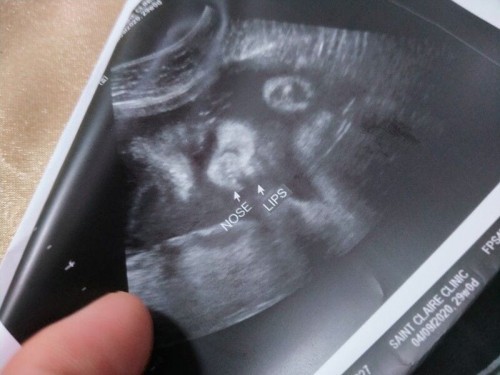

ULTRASOUND

mga momsh... bakit ganun paramg bilog or.pig nose baby ko. hahahaha diko matanong sa ob kasi parang ang vain pero na bobother ako sa ilong. parang bilog tas ang laki. fluid lang ba yan or ayan talaga ilong nya?? hahaha#firstbaby #pregnancy #1stimemom